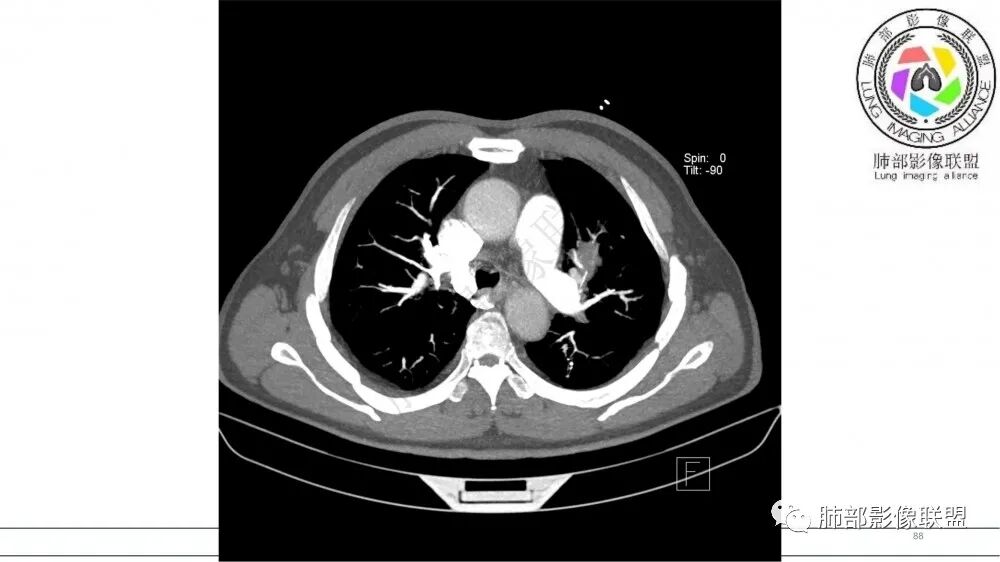

【每日晨读】上肺有强化的“指套征”

2021年8月6日晨读病例结果:小细胞肺癌

指套征:是影像征象,胸部平片表现为手指状密度增高影,以肺门为中心呈放射状分布,CT显示扩张支气管内低密度黏液栓形成或实性病变,呈管状、树枝状或卵圆形密度增高影;支气管扩张伴近端梗阻时,扩张支气管内部黏液分泌物不能排出而形成。可以伴随远端空气潴留征、阻塞性炎症。

研究报道,中心型 SCLC 经 CT 扫描后通常支气管表现为鼠尾样狭窄,肺门或纵隔肿块明显,由于肿块沿管壁生长表现为顺延支气管形态的不规则形状。病灶相对特征性影像学表现比如鸭蹼状、腊肠状、葫芦状及葡萄状改变,可以出现血管包埋,很少有空洞、空泡,较少引发肺不张,阻塞性炎症成都较轻。与一般肺癌比较,恶性程度高,侵袭力强、病灶很小就容易远处转移!Herzberg 等[19]研究指出,20%以上 SCLC 倍增时间短,预后不良。